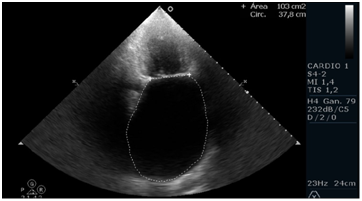

Patient of 75 years, height 165 cm and weight 72kg, with a history of mitral valve disease secondary to Rheumatic Fever. Percutaneous valvuloplasty was performed with balloon (Tecnica de Inoue) 6 years ago. Found in permanent atrial fibrillation(AF), NYHA functional class II, medicated with acenocoumarol, enalapril 10mg 2times/day, carvedilol 6.25mg 2times/day, spironolactone 25mg/day, furosemide 20mg/day and rosuvastatin 20mg/day. A Doppler echocardiogram is requested for dyspnea. It highlights the great biatrial dilatation to left predominance with moderate to severe mitral regurgitation, thickened mitral valve with characteristic stiffness (anterior valve in hockey stick), mitral stenosis moderated to severe by hemipresion time (THP) with an average of 10 beats (per to be found in atrial fibrillation rhythm) and systolic pressure in the pulmonary artery of 47mmHg. Left ventricular systolic function preserved. The left atrium measures 10.7cm in the anterior-posterior direction, an area in 4 chambers of 109 cm and an area in 2 chambers of 102cm2, obtaining a volume by the biplane method of 778ml (428ml/m2), remarking that currently the normal area by echocardiography is less than 34ml/m2.1 He presented with upper gastrointestinal bleeding with third episode of significant bleeding in 2 months that required blood transfusion due to gastric and duodenal ulceration. Mitral valve replacement is proposed with biological prosthesis, reduction of atrial volume, closure of left atrial appendage and isolation of pulmonary veins (Figure 1-3).

Figure 2 Apical echocardiographic view of four cameras with left atrial area measurement widely increased (109 cm2) and inferosuperior distance of 12.8 cm